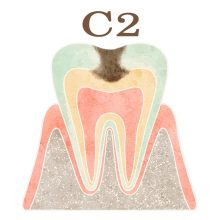

「C」とは歯科検診でよく使われる記号で、”caries”(カリエス、つまり虫歯)の頭文字を表します。「C」の後につくアルファベット(O)や数字(1,2,3,4)は、虫歯の進行具合を示します。

・C2(シーツー): 虫歯がエナメル質の下にある象牙質に進行した段階を指します。この段階では、虫歯の症状がより明確に現れます。この段階の虫歯は、早めの治療が重要です。虫歯の進行を止め、歯を健康な状態に戻すためには、歯科医の診断と治療が必要になります。